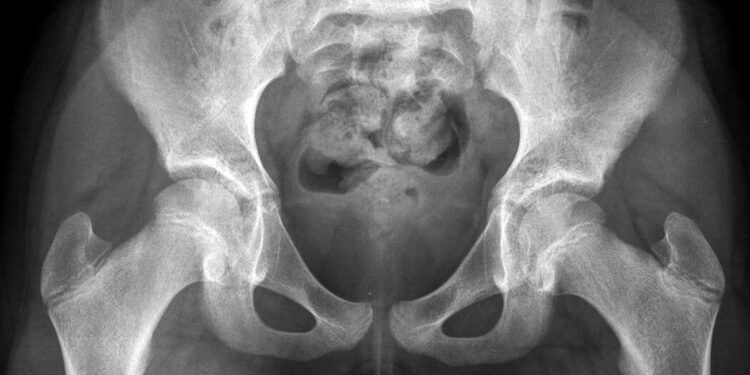

The critical issue is that the pelvis of a child is too small to allow passage of even a small fetus, said Dr. Ashok Dyalchand, who has worked with pregnant adolescent girls in low-income communities in India for more than 40 years.

“They have long labor, obstructed labor, the fetus bears down on the bladder and on the urethra,” sometimes causing pelvic inflammatory disease and the rupture of tissue between the vagina and the bladder and rectum, said Dr. Dyalchand, who heads an organization called the Institute of Health Management Pachod, a public health organization serving marginalized communities in central India.

“It is a pathetic state particularly for girls who are less than 15 years of age,” he added. “The complications, the morbidity and the mortality are much higher in girls under 15 than girls 16 to 19 although 16 to 19 has a mortality twice as high as women 20 and above.”

In the cases he has seen, early pregnancy arrests the very young mother’s physical growth, and also often her mental development because many girls leave school and lose normal social interaction with peers, he said. But while an anemic mother struggles to carry the pregnancy, fetuses appropriate nutrients and continue to grow, until they have well surpassed what a young mother’s pelvis can deliver.

“They go to labor for three days, four days, five days, and after that labor, usually the baby is dead. And then when the head is collapsed, then the baby is delivered,” said Dr. Syed, who is one of South Asia’s pre-eminent experts on the repair of obstetric fistula, a common outcome of obstructed labor in pregnant girls.